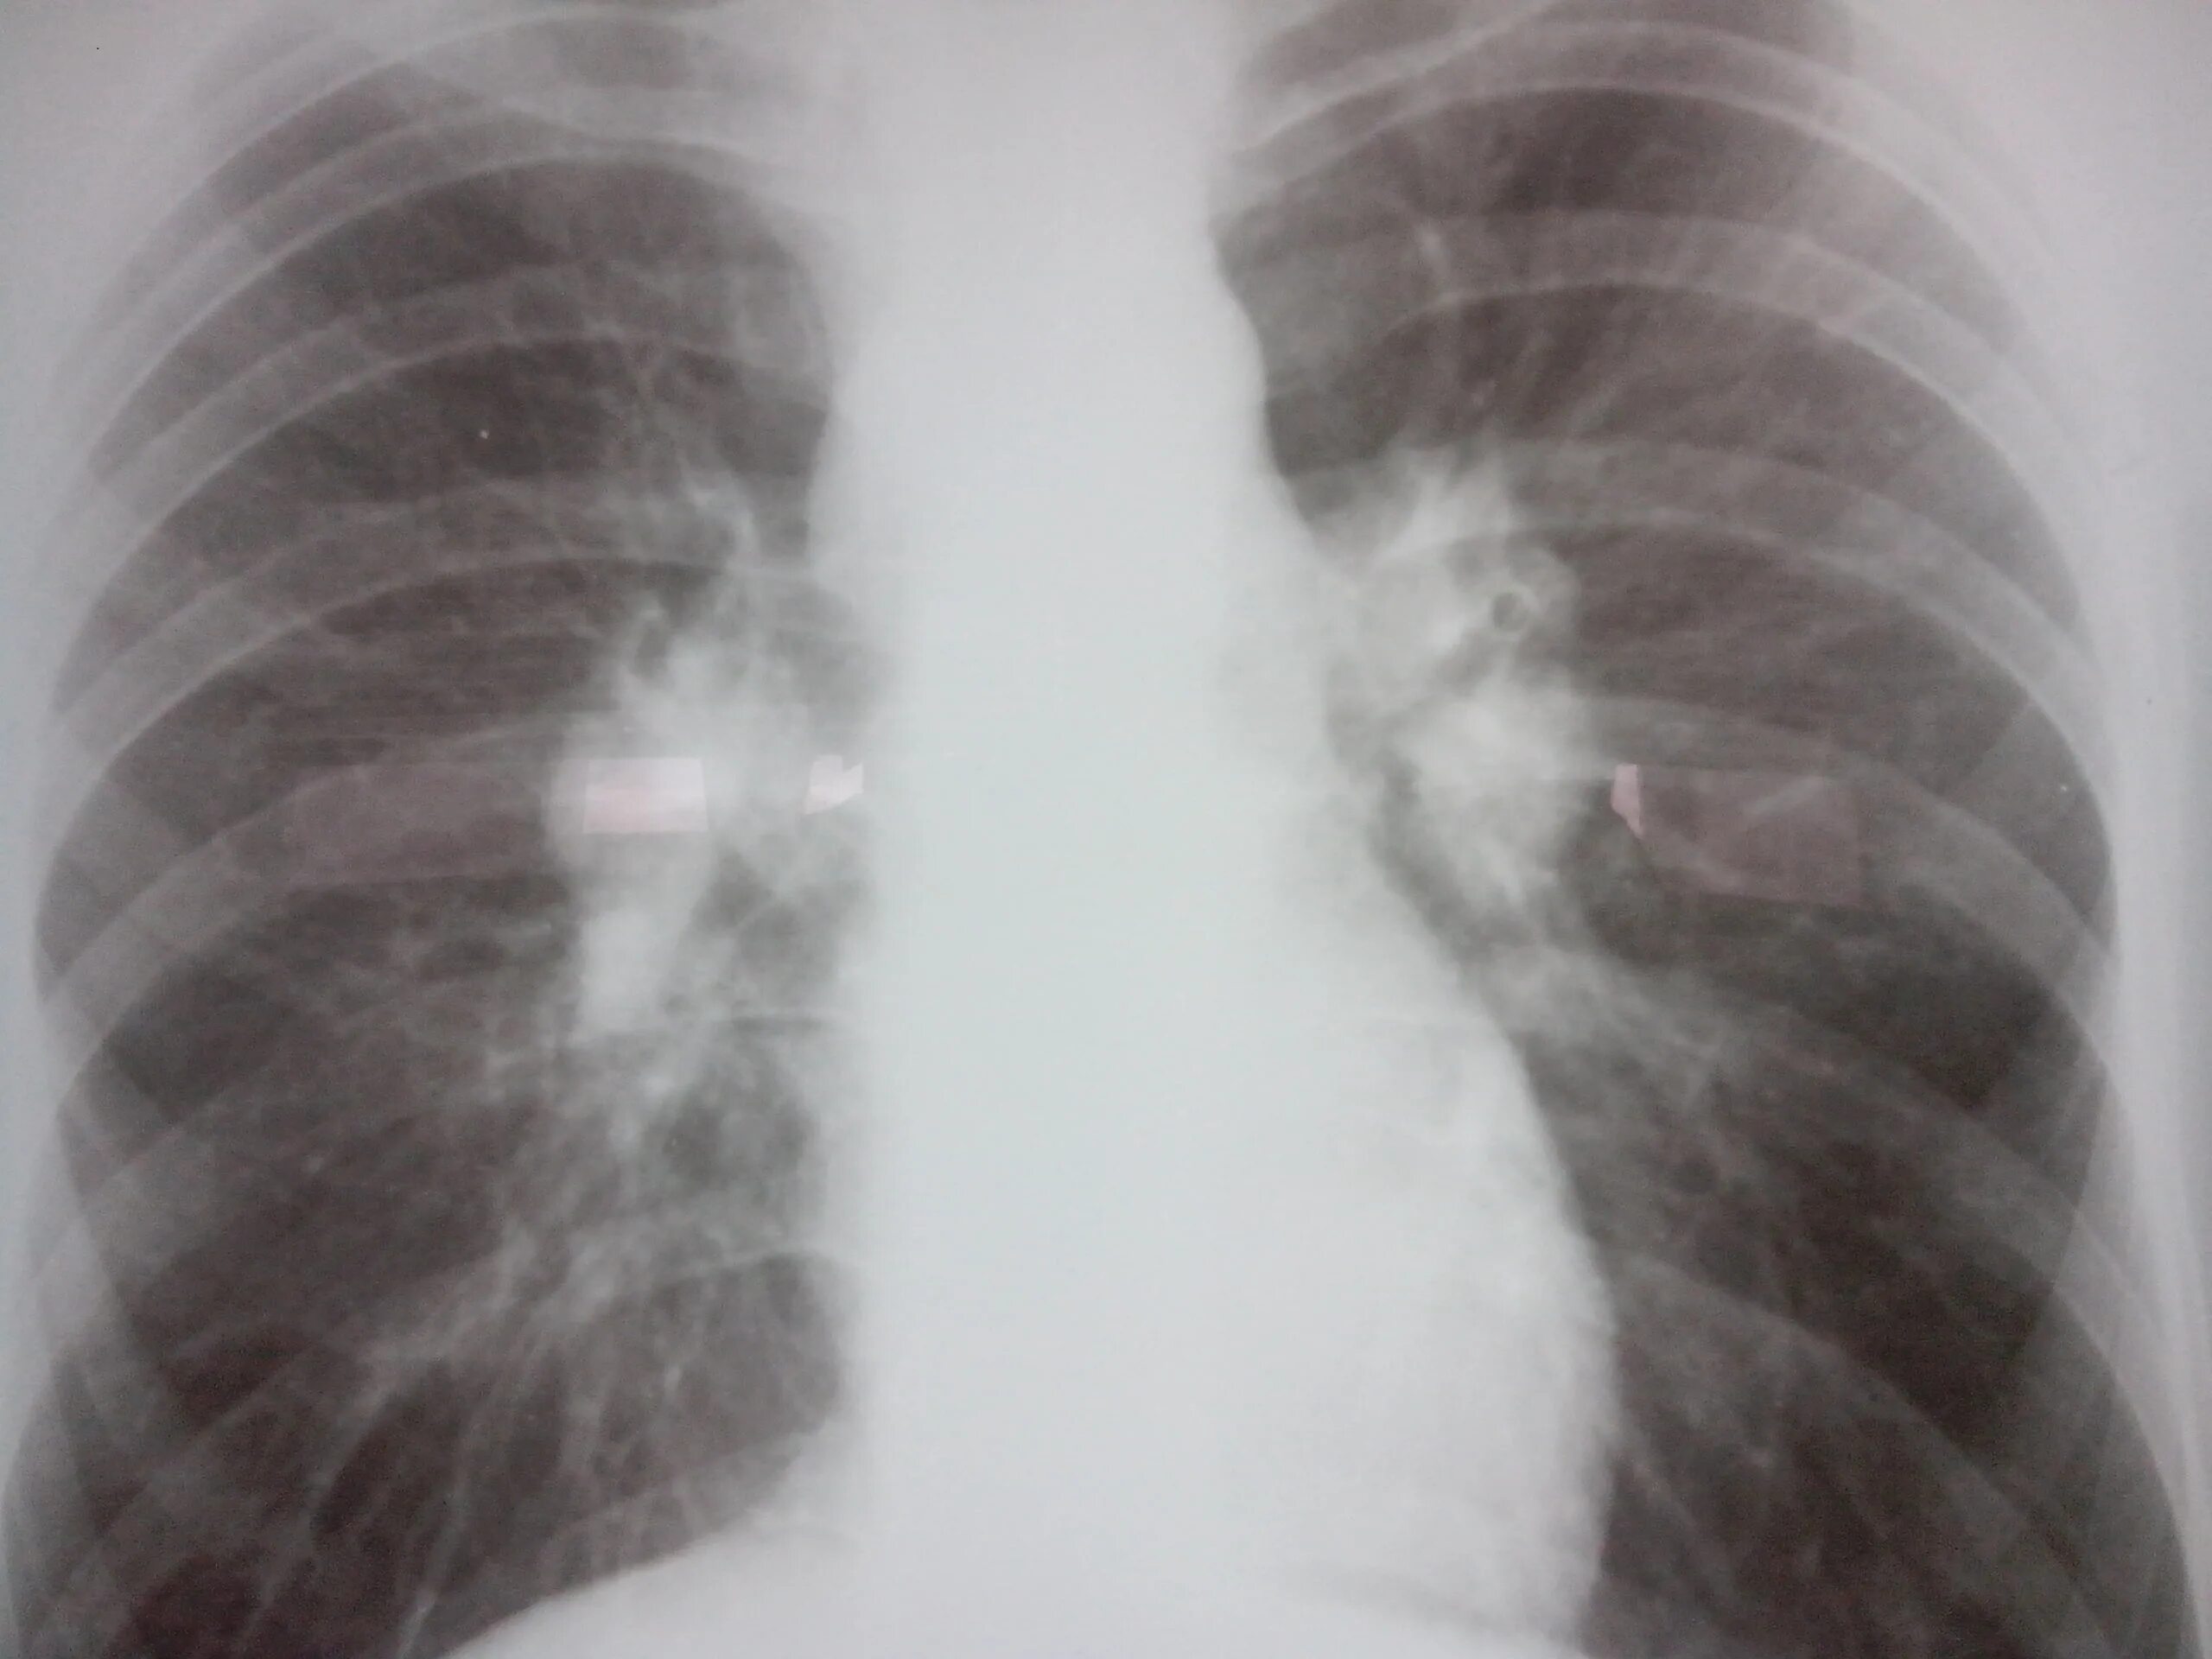

Бронхоаденит это